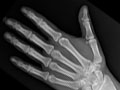

An extremity X-ray is a picture of your hand, wrist, arm, foot, ankle, knee, hip, or leg. It is done to see whether a bone has been fractured or a joint dislocated. It is also used to check for an injury or damage from conditions such as an infection, arthritis, bone growths (tumours), or other bone diseases, such as osteoporosis.

Extremity X-rays are done to:

• Find the cause of pain in an extremity.

• See if your bone is fractured or your joint is dislocated.

• See if fluid has built up in the joint or around a bone.

• See if your bones are positioned properly after treatment for a fracture or dislocation, such as after placing a cast or splint on an arm or leg. An X-ray also may be done after a doctor places a device such as a pin or an artificial joint in a bone.

• Find changes in your bones caused by conditions such as an infection, arthritis, bone growths (tumours), osteoarthritis of the hip, osteoarthritis of the knee, or other bone diseases.

• Find foreign objects such as pieces of glass or metal.

• Check to see if a child's bones are growing normally.

• See if your bones and joints are in the correct position after joint replacement surgery.